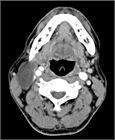

1. 頸部嚢胞性疾患は、先天性と後天性に区分される。先天性疾患は、小児・若年者の疾患であり、発生に沿った局所部位に波動を伴う腫瘤として確認される。これらの病態の理解には発生学の知識が必要になる。また、実際に臨床上の「嚢胞性」のなかに、画像上は充実性にみえる場合(蛋白濃度が高い内容液や血液を含む嚢胞)や、充実性腫瘍(脂肪腫は柔らかいため嚢胞性腫瘤の理学的所見を呈している)も含まれる。ただ、一般的に嚢胞とは分泌物が袋状に貯まる病態を指す( G)。

1. 頭頸部画像診断上、位置、形状、大きさ、壁の性状、境界、隔壁の有無、充実性部分や石灰化の有無、発生部位と進展範囲などが評価される。